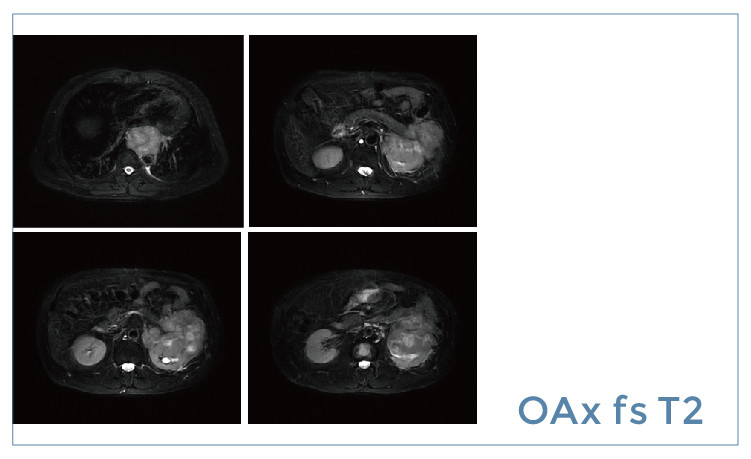

【朗润影像档案】20190614磁共振影像病例结果讨论

【朗润影像档案】磁共振影像病例分享(编号20190614)